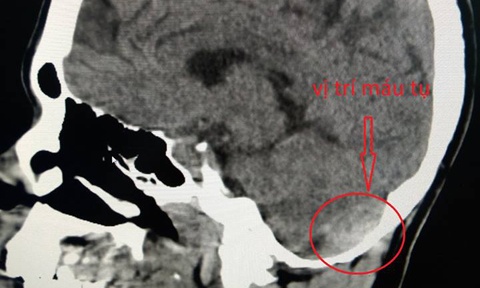

Ngay lập tức, bệnh nhân được các bác sĩ thăm khám kích hoạt báo động đỏ toàn viện. Các bác sĩ chuyên khoa Ngoại Thần kinh và Ngoại Tổng quát nhanh chóng có mặt, chẩn đoán bệnh nhân bị tụ máu ngoài màng cứng vùng chẩm phải, vỡ gan độ 4. Tất cả cùng hội chẩn và ra quyết định phải phẫu thuật cấp cứu để tranh thủ thời gian vàng và tránh tình trạng mất máu cho bệnh nhân.

| Bệnh nhân bị tụ máu ngoài màng cứng. Ảnh: BVCC |

Cả hai vị trí tổn thương đều cần được xử lý nhưng không thể phẫu thuật cùng lúc vì yêu cầu hai tư thế khác nhau. Do đó, trong quá trình hội chẩn, các bác sĩ hai khoa đã cùng thảo luận và đưa ra quyết định ưu tiên cho khoa Ngoại Thần kinh lấy máu tụ ngoài màng cứng cho bệnh nhân trước vì nguy cơ đe dọa tụt não rất cao nếu không được phẫu thuật sớm.

Trong tư thế nằm sấp, sau một tiếng được phẫu thuật tích cực, khối máu tụ ở vùng hố sau đầu của bệnh nhân đã được lấy ra hoàn toàn, loại bỏ nguy cơ tụt não và chèn ép cho bệnh nhân. Sau đó, bệnh nhân được nằm ngửa lại để tiến hành mở ổ bụng, lấy toàn bộ máu đông trong ổ bụng và khâu gan cầm máu.